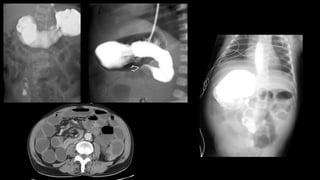

Íleo Meconial

• Obstrução por mecônio espesso no íleo terminal

• Fibrose cística

• Presente em 90% dos pacientes com íleo meconial

• Apresentação inicial em 15-20%

Neuhauser

• Complicações pré-natais:

• Perfuração – peritonite meconial

• Cistos meconiais

• Atresias intestinais

• Volvo

• Feminino, 2 dias

de vida, com

resíduos biliosos

em sonda

nasogástrica

Íleo Meconial • Obstruçãopor mecônio espesso no íleo terminal • Fibrose cística • Presente em 90% dos pacientes com íleo meconial • Apresentação inicial em 15-20% Neuhauser

Íleo Meconial • Complicaçõespré-natais: • Perfuração – peritonite meconial • Cistos meconiais • Atresias intestinais • Volvo

Íleo Meconial • Feminino,2 dias de vida, com resíduos biliosos em sonda nasogástrica